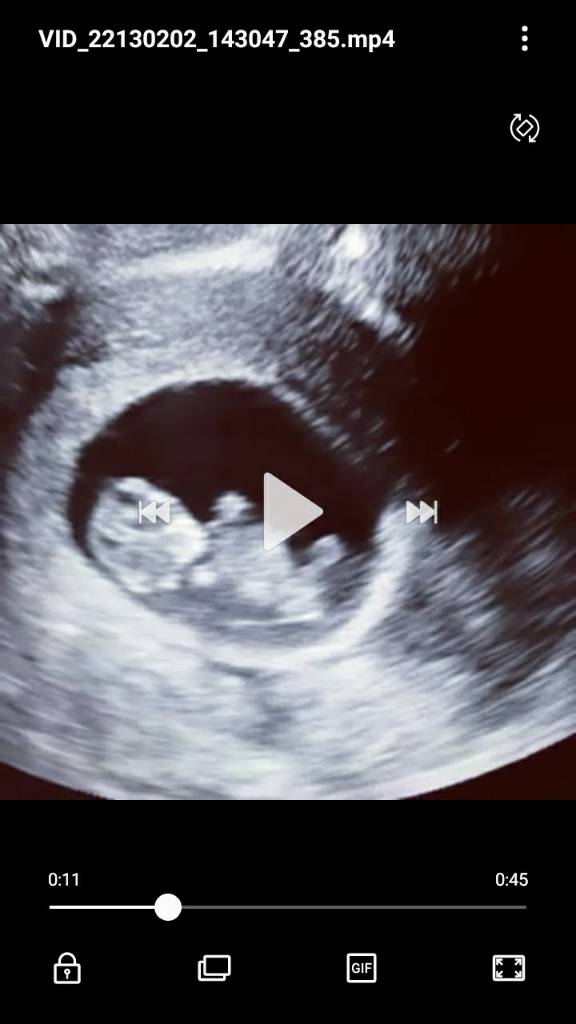

tylko chcę sobie pooglądać